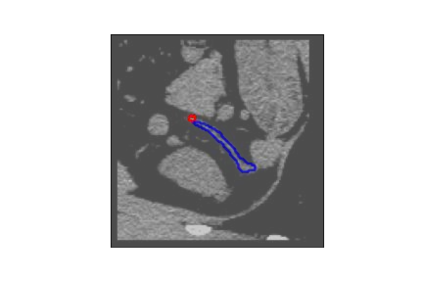

The human annotations are imperfect, especially when produced by junior practitioners. Multi-expert consensus is usually regarded as golden standard, while this annotation protocol is too expensive to implement in many real-world projects. In this study, we propose a method to refine human annotation, named Neural Annotation Refinement (NeAR). It is based on a learnable implicit function, which decodes a latent vector into represented shape. By integrating the appearance as an input of implicit functions, the appearance-aware NeAR fixes the annotation artefacts. Our method is demonstrated on the application of adrenal gland analysis. We first show that the NeAR can repair distorted golden standards on a public adrenal gland segmentation dataset. Besides, we develop a new Adrenal gLand ANalysis (ALAN) dataset with the proposed NeAR, where each case consists of a 3D shape of adrenal gland and its diagnosis label (normal vs. abnormal) assigned by experts. We show that models trained on the shapes repaired by the NeAR can diagnose adrenal glands better than the original ones. The ALAN dataset will be open-source, with 1,594 shapes for adrenal gland diagnosis, which serves as a new benchmark for medical shape analysis. Code and dataset are available at https://github.com/M3DV/NeAR.